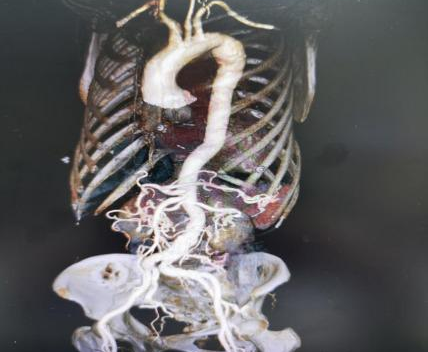

经过全面评估,专家团队最终敲定方案:实施经典的「Bentall 手术」(升主动脉带瓣管道置换术 + 冠状动脉移植术)。

石磊副主任医师解释,手术要在深低温停循环的体外循环支持下,先把病变的升主动脉和「罢工」的主动脉瓣一起切除;再用一个『人工带瓣管道』(即人工血管和人工瓣膜的复合体)来重建患者的『心脏出口』和『生命主干道』;最关键的一步,是要把供应心脏自身供血的左右冠状动脉,精确移植到新的人工血管上。